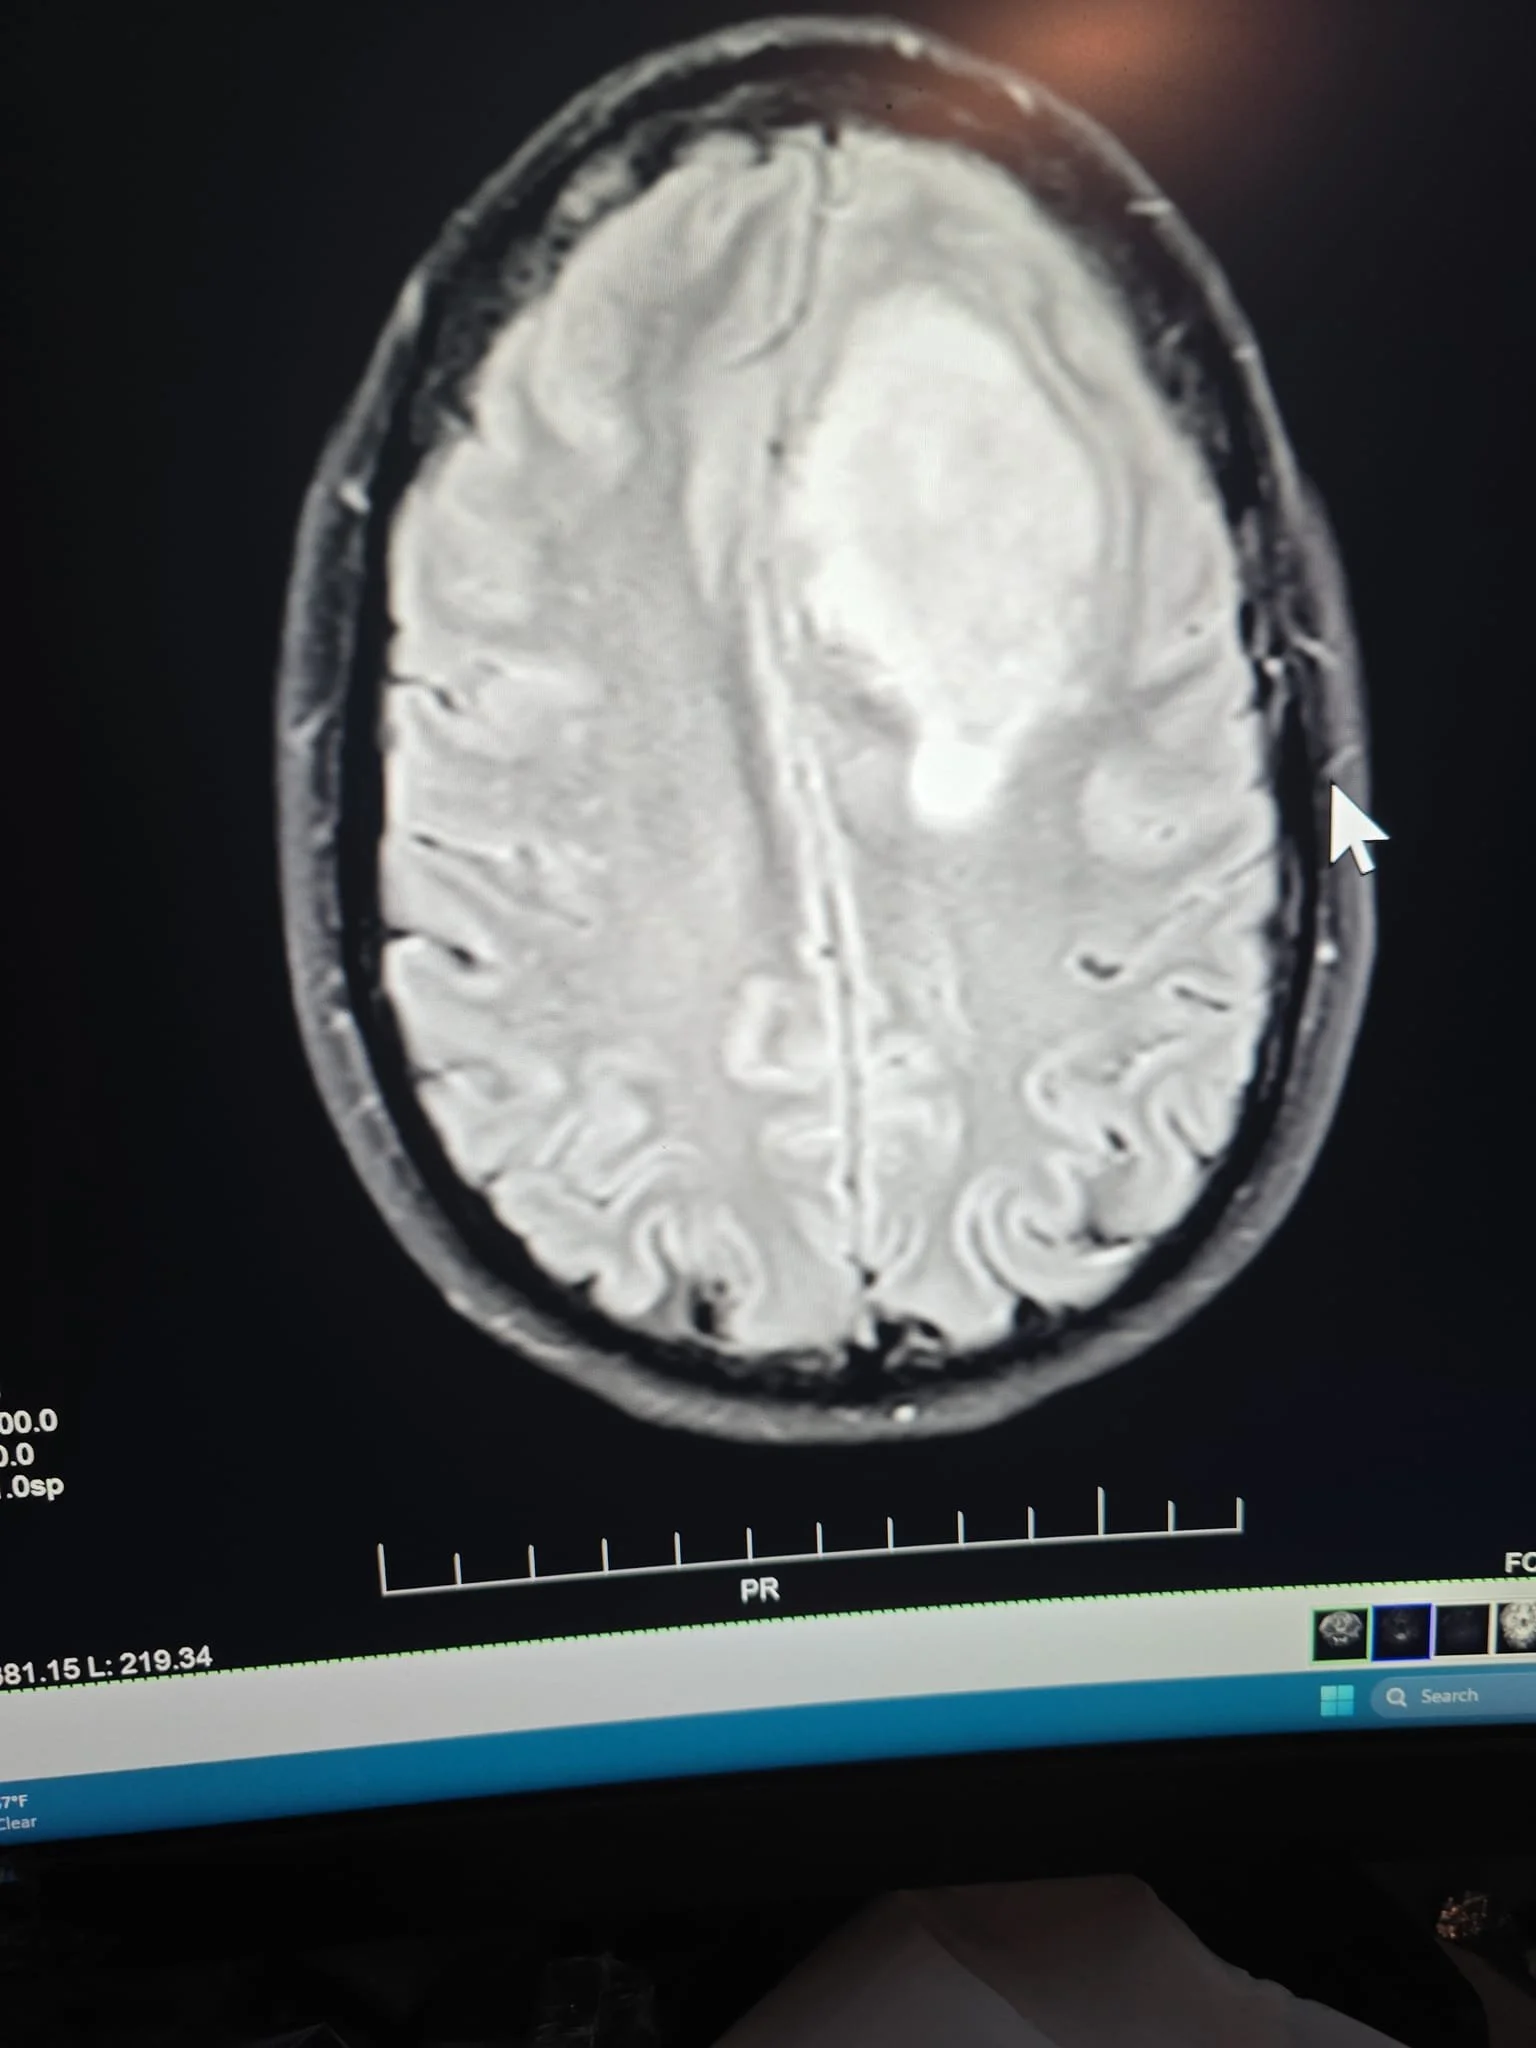

But he didn't have the wrong person. The scans were clear: a huge tumor, taking up a quarter of my brain. My fiancée and I sat there, staring at the images, the silence broken only by the frantic beating of my heart. Panic set in, a cold, icy dread. I looked at my fiancée, and I could see the fear mirrored in her eyes. All I could think was, "Am I going to die?"

And the tumor? It was more like two, with a little "baby tail" connecting them. A real family reunion up there. And until they were removed, we wouldn't know if they were cancerous.